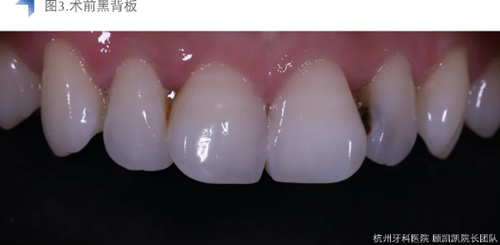

考慮到術前口內(nèi)檢查及影像學檢查提示齲損較近髓,與患者溝通可能設計牙髓治療??紤]到美學及長期穩(wěn)定考量,與患者溝通直接樹脂充填與間接瓷貼面修復兩種修復方式,患者考慮后決定采用間接椅旁瓷貼面修復。

局麻橡皮障下去齲盡,極盡髓,iroot bp+蓋髓,上面覆蓋bisco硅酸鈣,流體樹脂洞型重建后貼面預備,排齦后Cerec Omincam光學取模,3D打印樹脂模型以檢查修整瓷貼面。